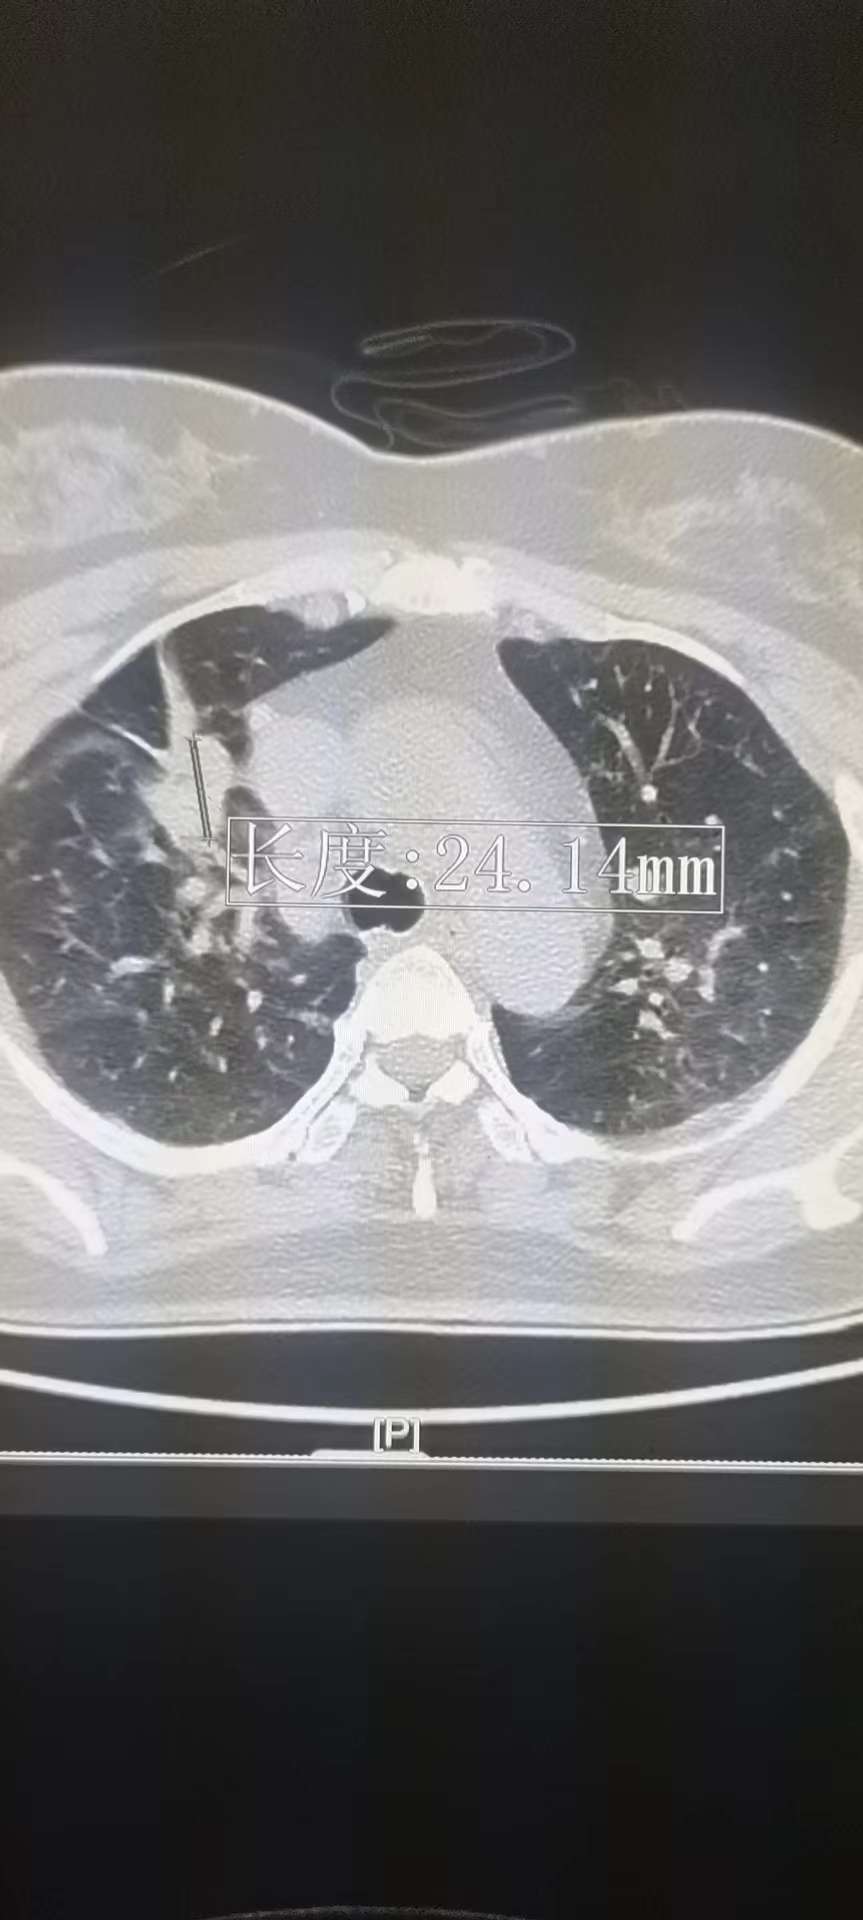

有没有会看ct片子的

因为换医院了 所以没有办法对比之前的片子 。希望会的帮忙看一下谢谢了!

这四张是7月份的

这四张是9月份的

打电话问了 根据原先位置出了新结果 中间还闹了乌龙给我测量位置不对出了个45mm多,真的无语了!

9月的没有标明右肺上叶病灶大小呢?